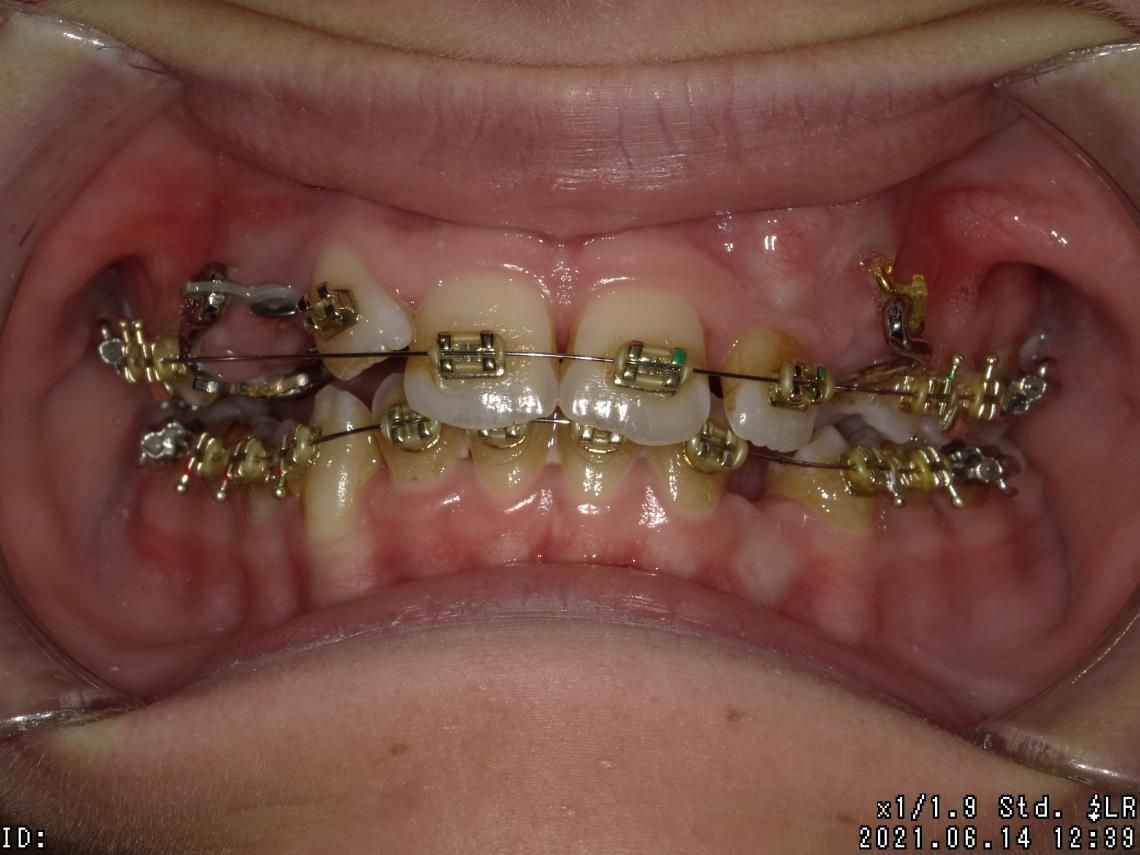

LES BAGUES

Cet appareil dentaire fixe est composé de brackets ou bagues, sortes de petits boutons en métal, en plastique ou en céramique, collés sur les dents et reliés par un fil. Il permet de déplacer les dents du patient dans la direction optimale, de les réaligner au fur et à mesure, de traiter des cas complexes de manque de place et des dents retenues ou dystopiques. Le traitement est moins tributaire de la coopération du patient.